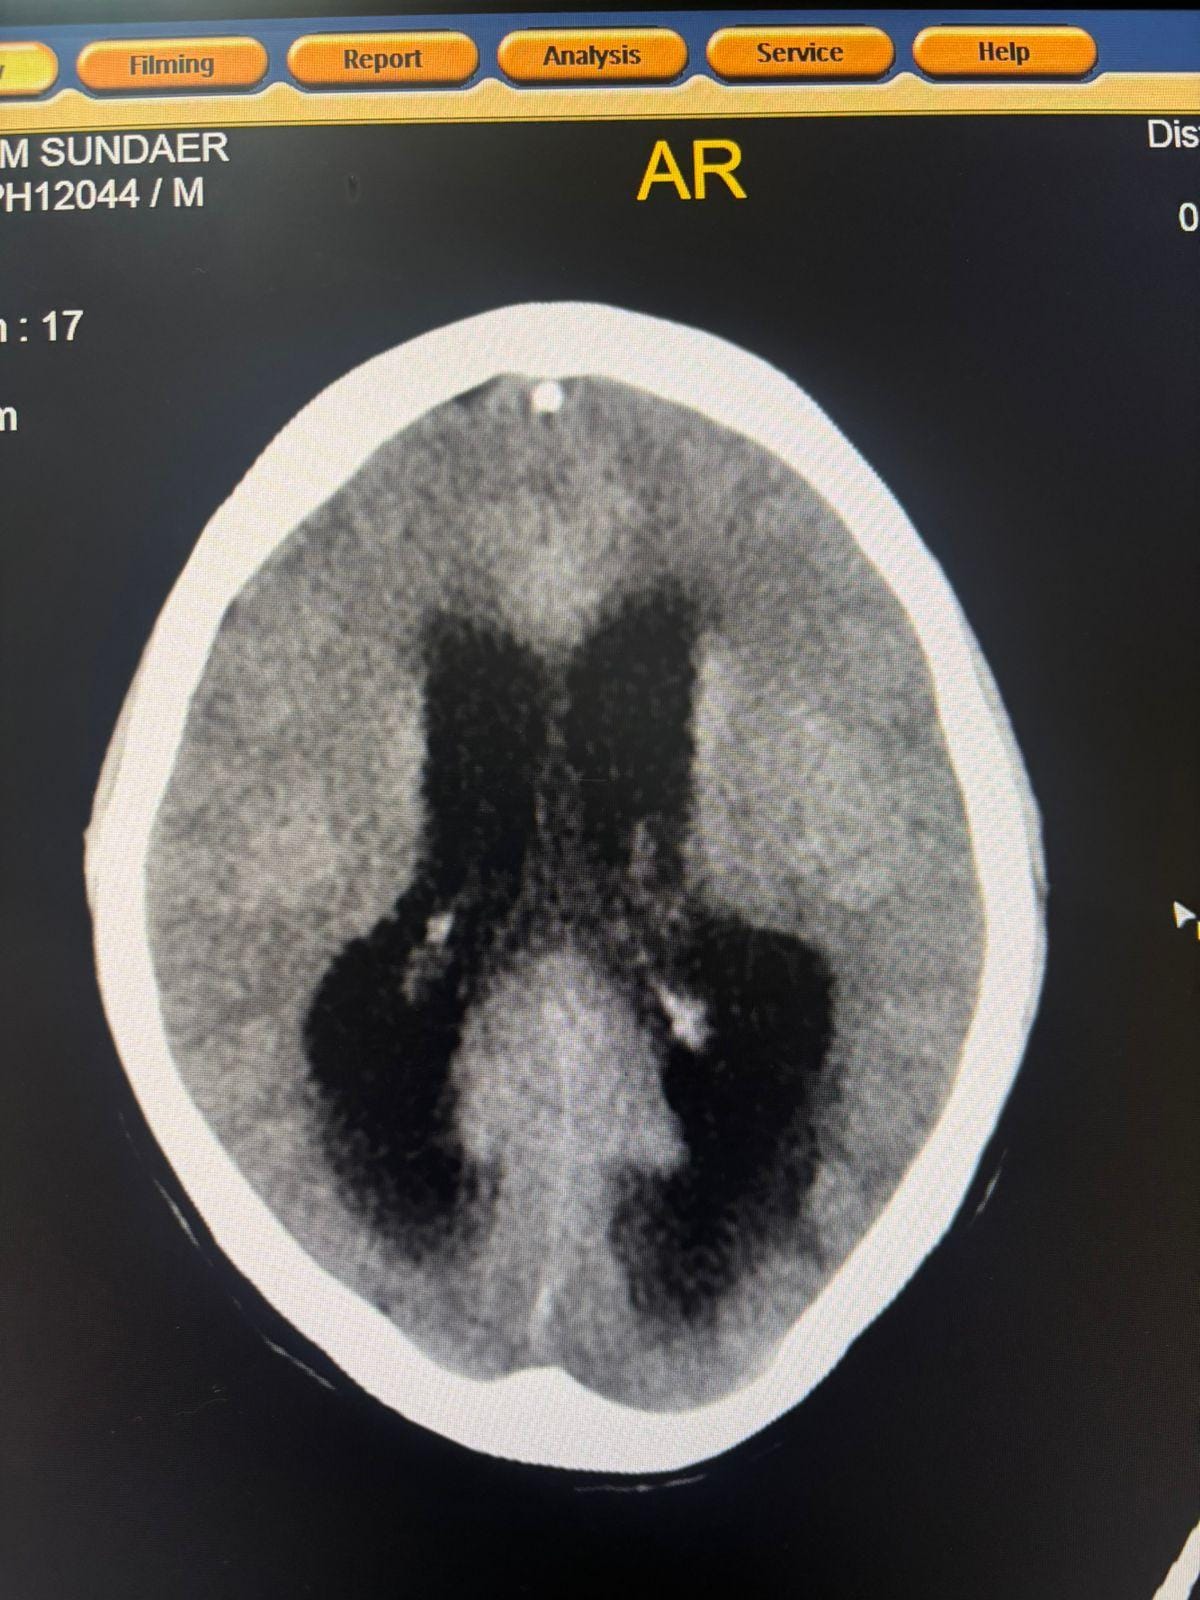

स्टेज–4 ब्रेन टीबी में कम होती है बचने की संभावना

चिकित्सकों के अनुसार स्टेज–4 ट्यूबरकुलस मेनिन्जाइटिस में मृत्यु दर अत्यंत अधिक होती है। दवा अधूरी छोड़ने के कारण मरीज में हाइड्रोसेफेलस विकसित हो गया, जिससे मस्तिष्क में सूजन आ गई और वह पूरी तरह अचेत हो गया। इस अवस्था से मरीज का सुरक्षित बाहर आना जिले के लिए बड़ी चिकित्सकीय उपलब्धि माना जा रहा है।